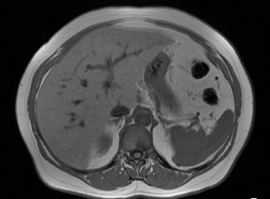

Embora a biópsia seja o padrão-ouro, métodos não invasivos podem ser considerados.

A análise histológica de material obtido por biópsia hepática segue como o padrão-ouro para o diagnóstico de NASH e para a determinação do grau de fibrose hepática, além de permitir, de fato, distinguir o NAFL da NASH. Contudo, trata-se de um método invasivo, com riscos inerentes ao procedimento, como sangramento intraperitoneal, hipotensão e dor, podendo ainda ser contraindicado para indivíduos com distúrbios de coagulação.

Ademais, o pequeno fragmento obtido pela biópsia não necessariamente reproduz o comprometimento de todo o fígado, pois as alterações teciduais podem ocorrer de forma heterogênea. Dessa forma, o método não serve como teste de rastreamento em pacientes com risco para DGHNA ou para avaliação periódica de progressão da doença.

Nesse cenário, preditores não invasivos foram desenvolvidos como alternativa, assim como métodos de imagem – a elastografia por ressonância magnética ou por ultrassonografia –, limitando a realização da biópsia apenas para casos específicos.